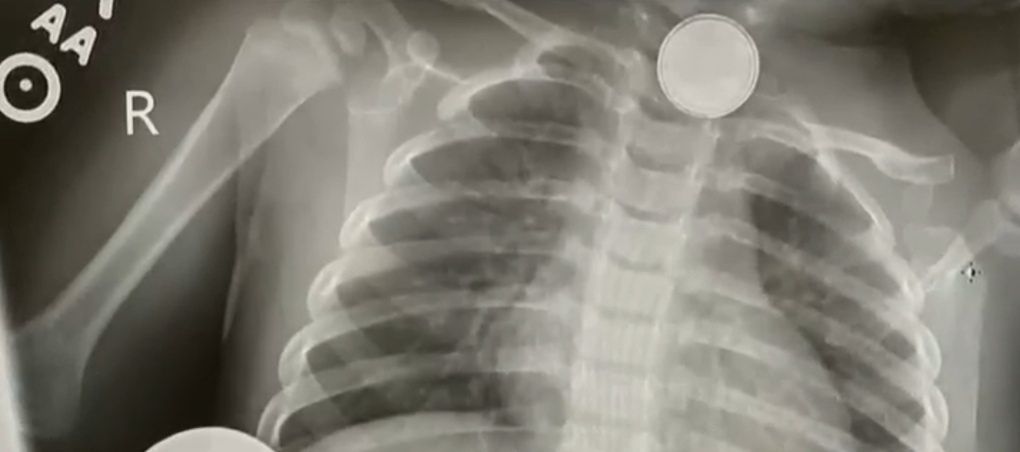

Stan dziewczynki pogarszał się. Po dwóch dniach od wizyty u lekarza matka dziecka Trista Hamsmith odkryła, że w pilocie brakuje małej baterii. Kobieta natychmiast zorientowała się, że objawy Resse wskazują na poparzenie baterią. Dziewczynka trafiła do szpitala, gdzie zrobiono jej prześwietlenie. Zdjęcia rentgenowskie potwierdziły, że Reese ma w przełyku baterię.

Bateria tkwiła w gardle Reese przez kilka dni.

Bateria tkwiła w gardle dziecka przez kilka dni przez co poważnie poparzyła jej gardło, przełyk i struny głosowe. 17-miesięczna Reese przeszła kilka operacji. Dziewczynka została przetransportowana z University Medical Center w Lubbock w Teksasie do Texas Children’s Hospital w Houston, gdzie zmarła kilka dni temu.